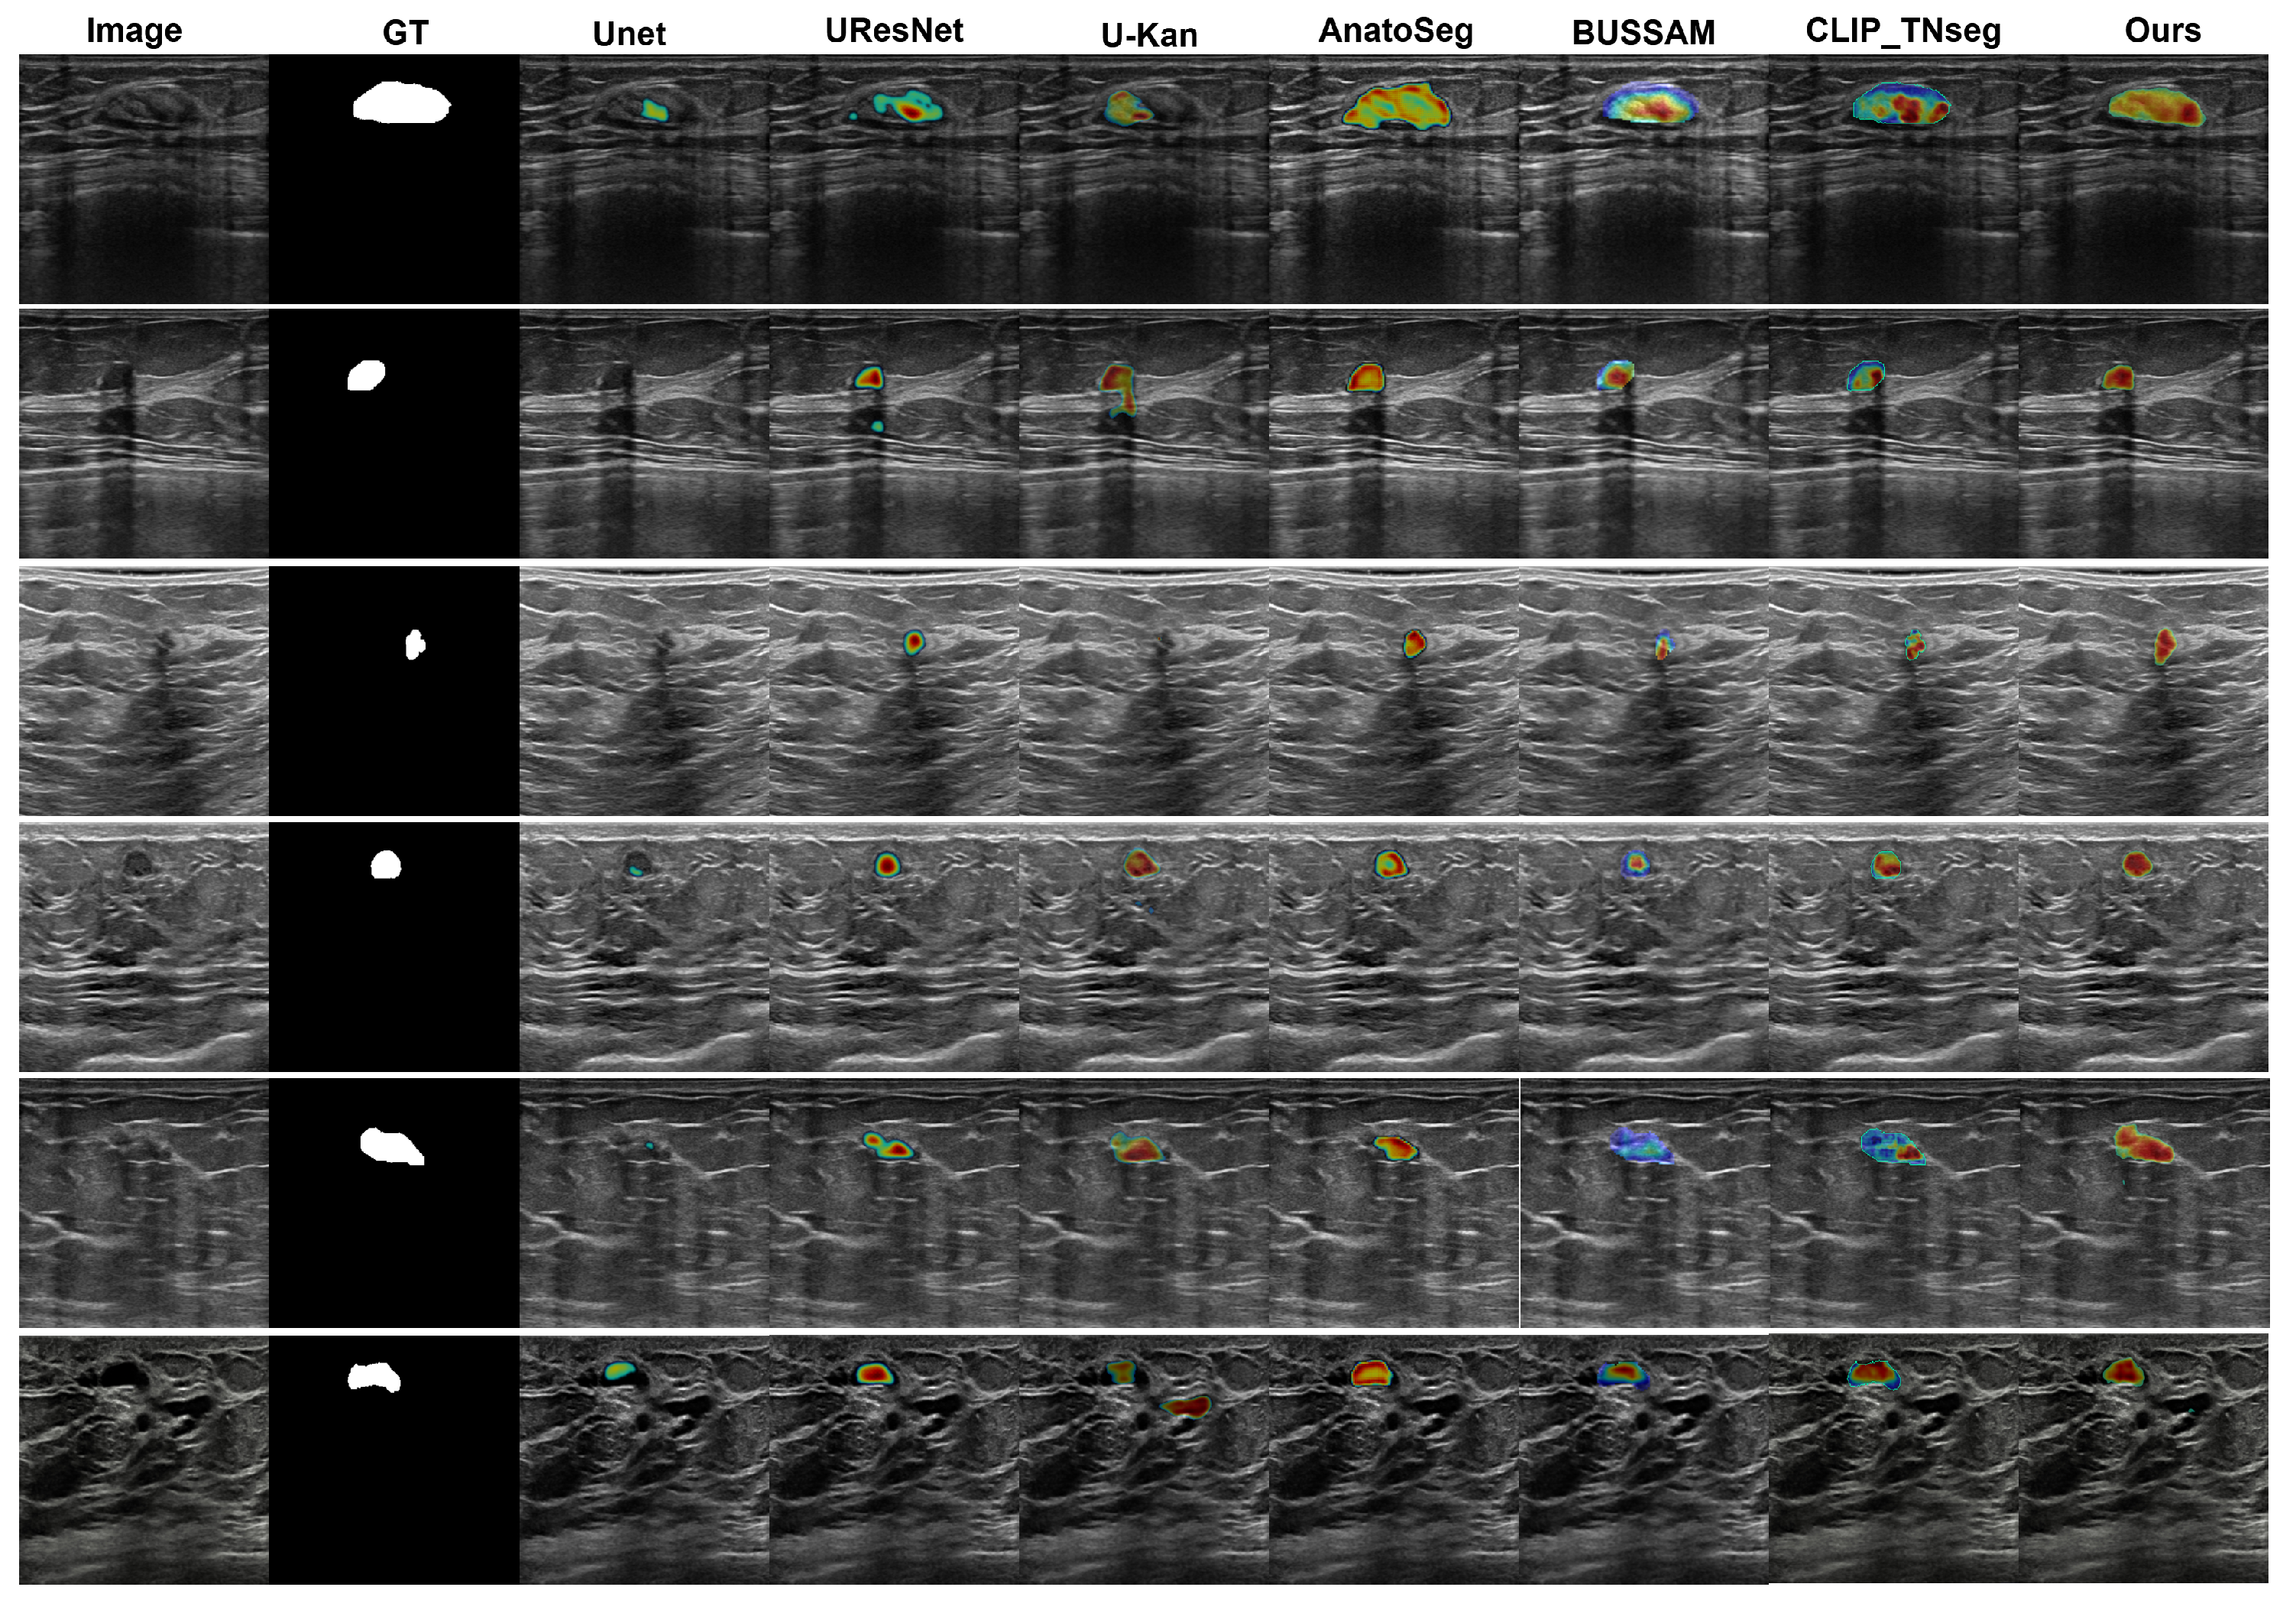

3.1.3. Qualitative Assessment

3.3. Qualitative Visualizations